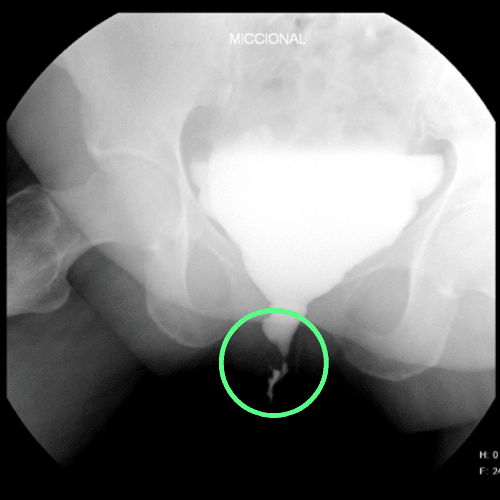

cistouretrografía que revela una estenosis en la porción bulbar de la uretra

Porción de la uretra ubicada entre la base del pene y el esfínter urinario. Esta porción es solo accesible desde el periné.